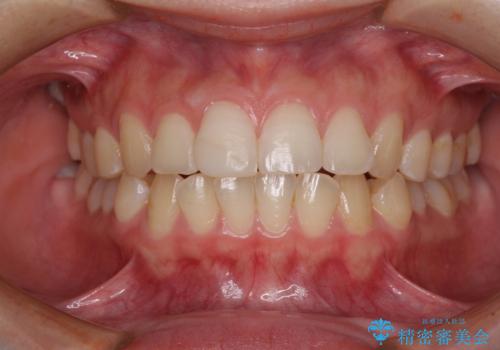

- 転んで前歯が欠けてしまったとのことで来院された患者様です。

転んで前歯の先端1/3ほどが欠けており、近医にて応急処置としてコンポジットレジン修復がされていました。

審美性や舌触り、今後の歯への負担などを考え、オールセラミッククラウンにて補綴治療を行うこととしました。